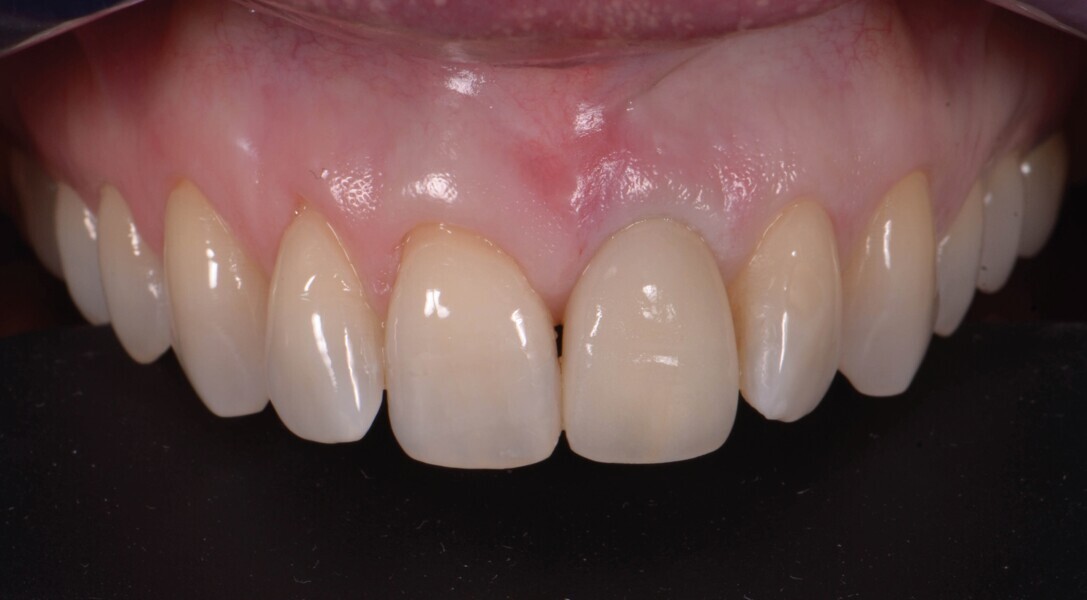

Fig. 20a : Couronne définitive implanto-portée, vue extraorale ;

Le transfert est donc mis en place en bouche (Fig. 18), et une empreinte est prise en technique pick-up, avec un porte-empreinte à ciel ouvert (Fig. 19). La couronne provisoire est remise en place rapidement, afin de prévenir toute rétraction des tissus mous. La couronne définitive en disilicate de lithium est ensuite mise en place (Fig. 20), et est vissée avec couple de serrage de 20 Ncm, conformément aux recommandations du fabricant.

Lors du suivi a cinq ans, on ne peut que constater le résultat esthétique maintenu (Fig. 21). La radiographie montre un niveau osseux stable et une connexion étroite entre l’implant et le pilier (Fig. 22).